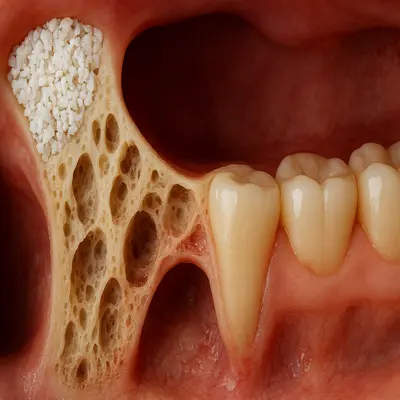

جراحی دندان عقل نهفته با دریل جراحی و نمای واقعی از استخوان فک

علاوه بر این، هرچه سن بالاتر میرود—بهویژه بعد از ۳۰ سالگی—استخوان متراکمتر میشود و ریشهها تکامل بیشتری پیدا میکنند؛ در نتیجه جراحی سختتر و دورهی نقاهت طولانیتر میشود.